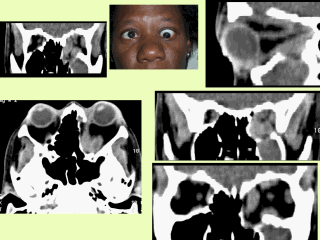

This female black patient, debuted with a severe left TO. In the scan, you can note enlargement of the inferior and medius rectus muscles. The right superior view, shows the optic nerve stretching which joined to above mentioned muscles, provoked an optic neuropathy in this case.